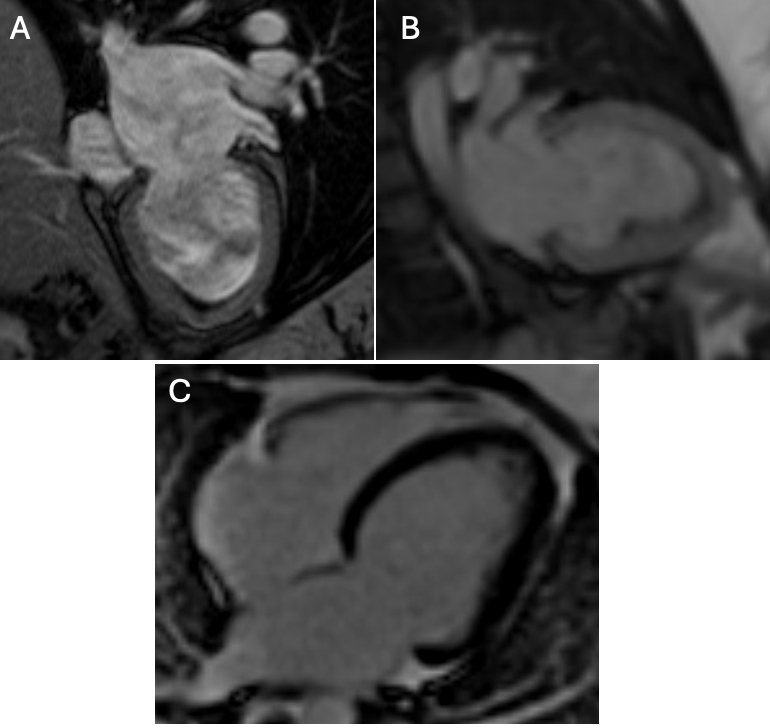

A 37-year-old woman with hypertension, polycystic ovarian syndrome, and a family history of eosinophilic esophagitis presented 8 weeks postpartum with progressive dyspnea and hypoxia. Laboratory testing showed mild eosinophilia and elevated BNP with a normal troponin. Transthoracic echocardiography revealed preserved ejection fraction and apical thickening. Cardiac MRI (1.5T) demonstrated reduced LVEF (43%), mid-to-apical akinesis, and a large laminar apical thrombus (18 × 51 mm). Native T1 and extracellular volume were elevated. First-pass perfusion showed an apical perfusion defect surrounded by hyperenhancing myocardium, consistent with the “double V sign.” Late gadolinium enhancement demonstrated mid-wall fibrosis in the basal anteroseptum. Endomyocardial biopsy revealed only mild myocyte hypertrophy without eosinophilic infiltration.

Eosinophilic myocarditis is an uncommon inflammatory cardiomyopathy that often mimics other etiologies of heart failure and may evade histologic confirmation due to patchy myocardial involvement. In this case, the clinical context and distinct cardiac MRI findings supported the diagnosis despite a non-diagnostic biopsy. Given the imaging and laboratory findings, high-dose corticosteroids and anticoagulation were initiated empirically. At three months, repeat imaging showed improved LVEF (57%), resolution of wall motion abnormalities, and thrombus shrinkage to 7 mm. By ten months, MRI demonstrated normalized systolic function (LVEF 60%), near-complete resolution of the thrombus (10 × 6 mm, tethered in the chordae), and no residual late enhancement. T1 and extracellular volume remained mildly elevated. This case illustrates the diagnostic and longitudinal value of cardiac MRI in eosinophilic myocarditis, particularly when biopsy is inconclusive, and highlights the utility of serial imaging in guiding and monitoring therapy.